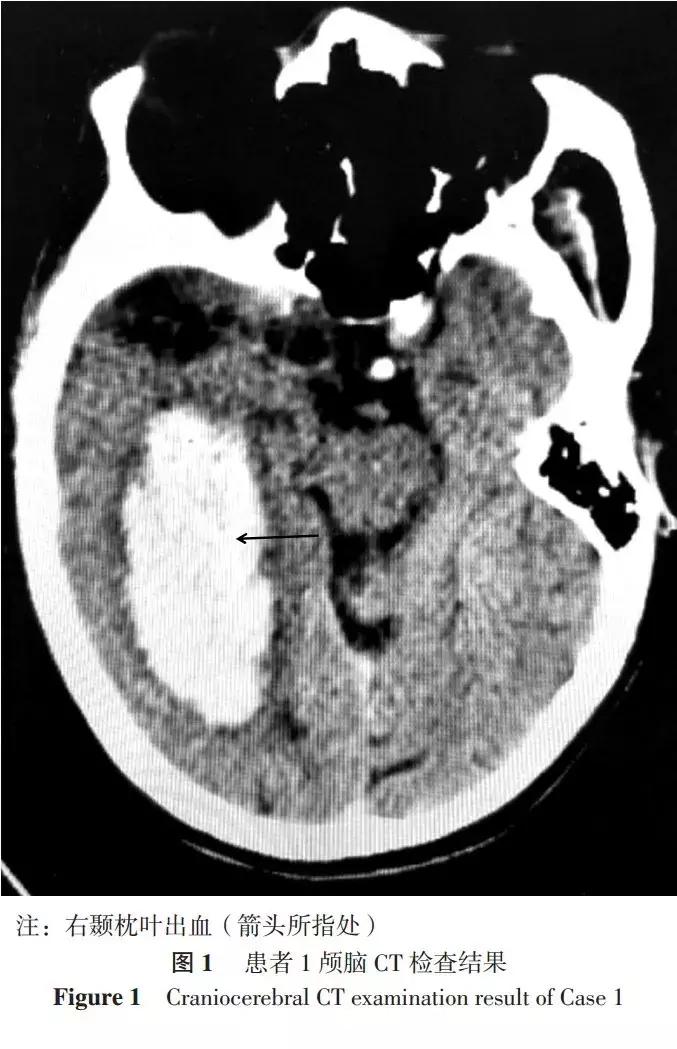

患者1,男,76岁,因“胸闷伴咽痛1周、加重1 d”于2015-02-04入住广东省中医院。患者既往有2型糖尿病、高脂血症病史。入院后测量血压为190/105 mm Hg(1 mm Hg=0.133 kPa),行心电图检查发现窦性心动过缓、下壁ST-T异常、r波递增不良,检测心肌肌钙蛋白T(cTnT)为3.198 μg/L。入院诊断:急性心肌梗死、高血压3级(很高危)、2型糖尿病、高脂血症,遂给予阿司匹林、氯吡格雷、替罗非班抗血小板聚集,依诺肝素抗凝,阿托伐他汀调脂、稳定斑块,泵注硝酸甘油扩张冠状动脉、降压药物治疗等。入院第3天患者行冠状动脉造影发现左主干末端狭窄率约为50%,左前降支近段闭塞,左回旋支开口至远段病变、狭窄率为90%~95%,第一对角支粗大、中段狭窄率约为90%,右冠状动脉中远段病变、远段狭窄率为95%~99%,遂于右冠状动脉从远至近植入2.50 mm×28.00 mm、3.00 mm×18.00 mm支架2枚,PCI*共中**使用普通肝素7 000 U。患者按计划于PCI后第4天行左回旋支PCI:第一对角支植入2.50 mm×18.00 mm支架1枚,左回旋支从远至近植入2.50×28.00 mm、2.50×33.00 mm支架2枚,术*共中**使用普通肝素7 000 U。第2次PCI后第2天患者突发左侧头痛,呈持续性剧烈刺痛,伴恶心呕吐,急查颅脑CT发现右颞枕叶出血(见图1),出血量约为63 ml,立即停用抗血小板聚集、抗凝药物,予以脱水、止血、控制血压、止呕治疗等并急请神经科会诊,但由于患者逐渐昏迷并很快出现脑疝,最终抢救无效死亡。